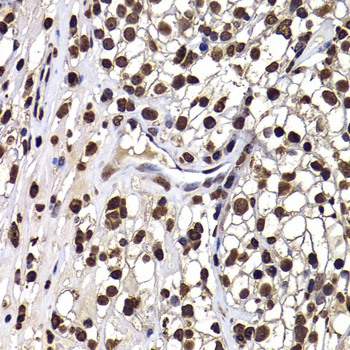

Immunohistochemistry of paraffin-embedded human well-differentiated squamous skin carcinoma using DNAJB6 antibody.

Immunohistochemistry of paraffin-embedded human kidney using DNAJB6 antibody.

Immunohistochemistry of paraffin-embedded human kidney cancer using DNAJB6 antibody.

Immunohistochemistry of paraffin-embedded human stomach using DNAJB6 antibody.

Immunohistochemistry of paraffin-embedded mouse ileum using DNAJB6 antibody.

IHC 1:50 - 1:200